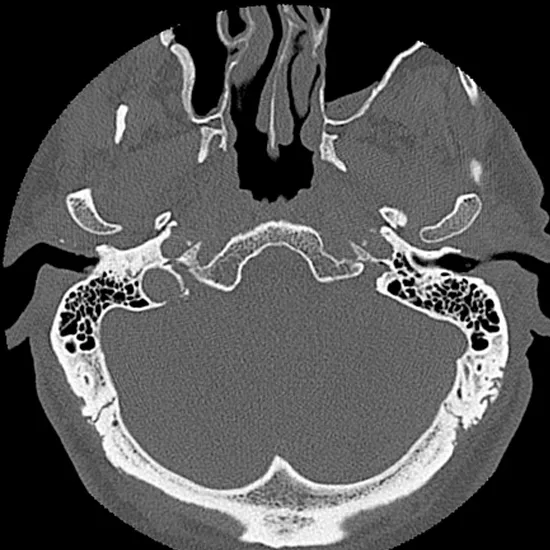

CT (Computed Tomography) Temporal Bone Coronal is an imaging scan to obtain images of the structure of both the inner and middle ear. It is used to identify the problems associated with both the inner and middle ear. It is used to diagnose conditions such as hearing loss, pulsatile tinnitus, external auditory canal atresia, middle ear inflammation, and temporal bone trauma.

• To assess the inner and middle ear structure.

• To diagnose conditions such as hearing loss, pulsatile tinnitus, external auditory canal atresia, middle ear inflammation, temporal bone trauma as well as the vascular tympanic membrane.

• To diagnose the problems associated with both the inner and middle ear.